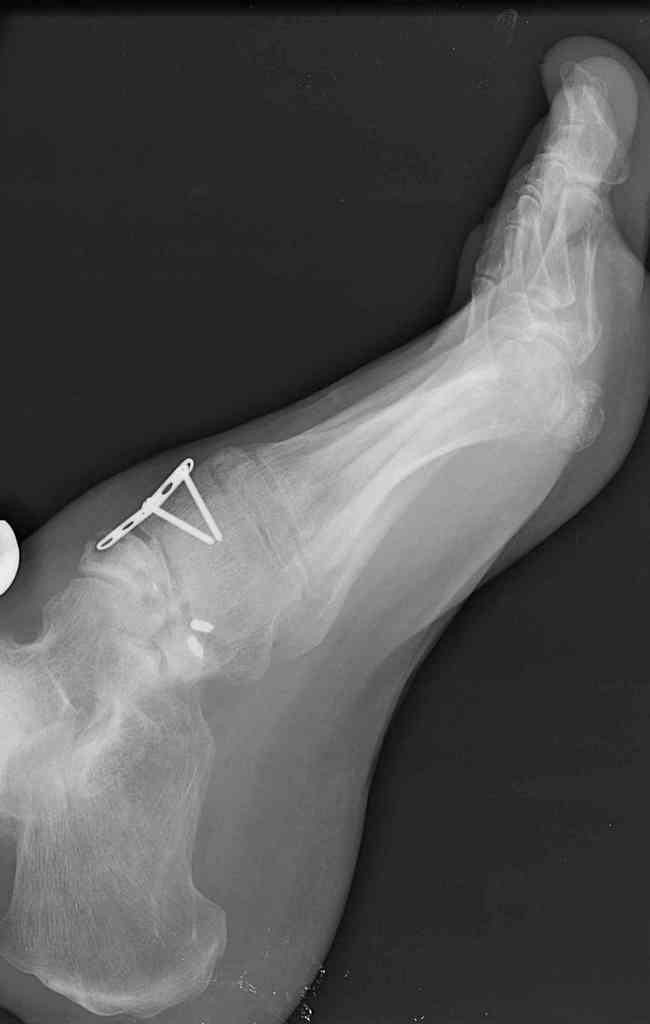

Navicular non-union

This is a 44 year old male laborer, smoker, who had his foot caught in a forklift about a year ago.

He had an ORIF and subsequent removal of hardware and presented to me with severe midfoot pain. His medial column is grossly unstable on exam but is passively correctable. Wounds are well healed, no sign of infection.

I haven't found much literature on salvage for this. What next? Iliac crest graft for structure with talo-navicular-cuneiform arthrodesis to restore the medial column? Will this fuse as an isolated procedure and given the loss of most of his subtalar motion, would a talocalcaneal arthrodesis improve his chances of fusion?